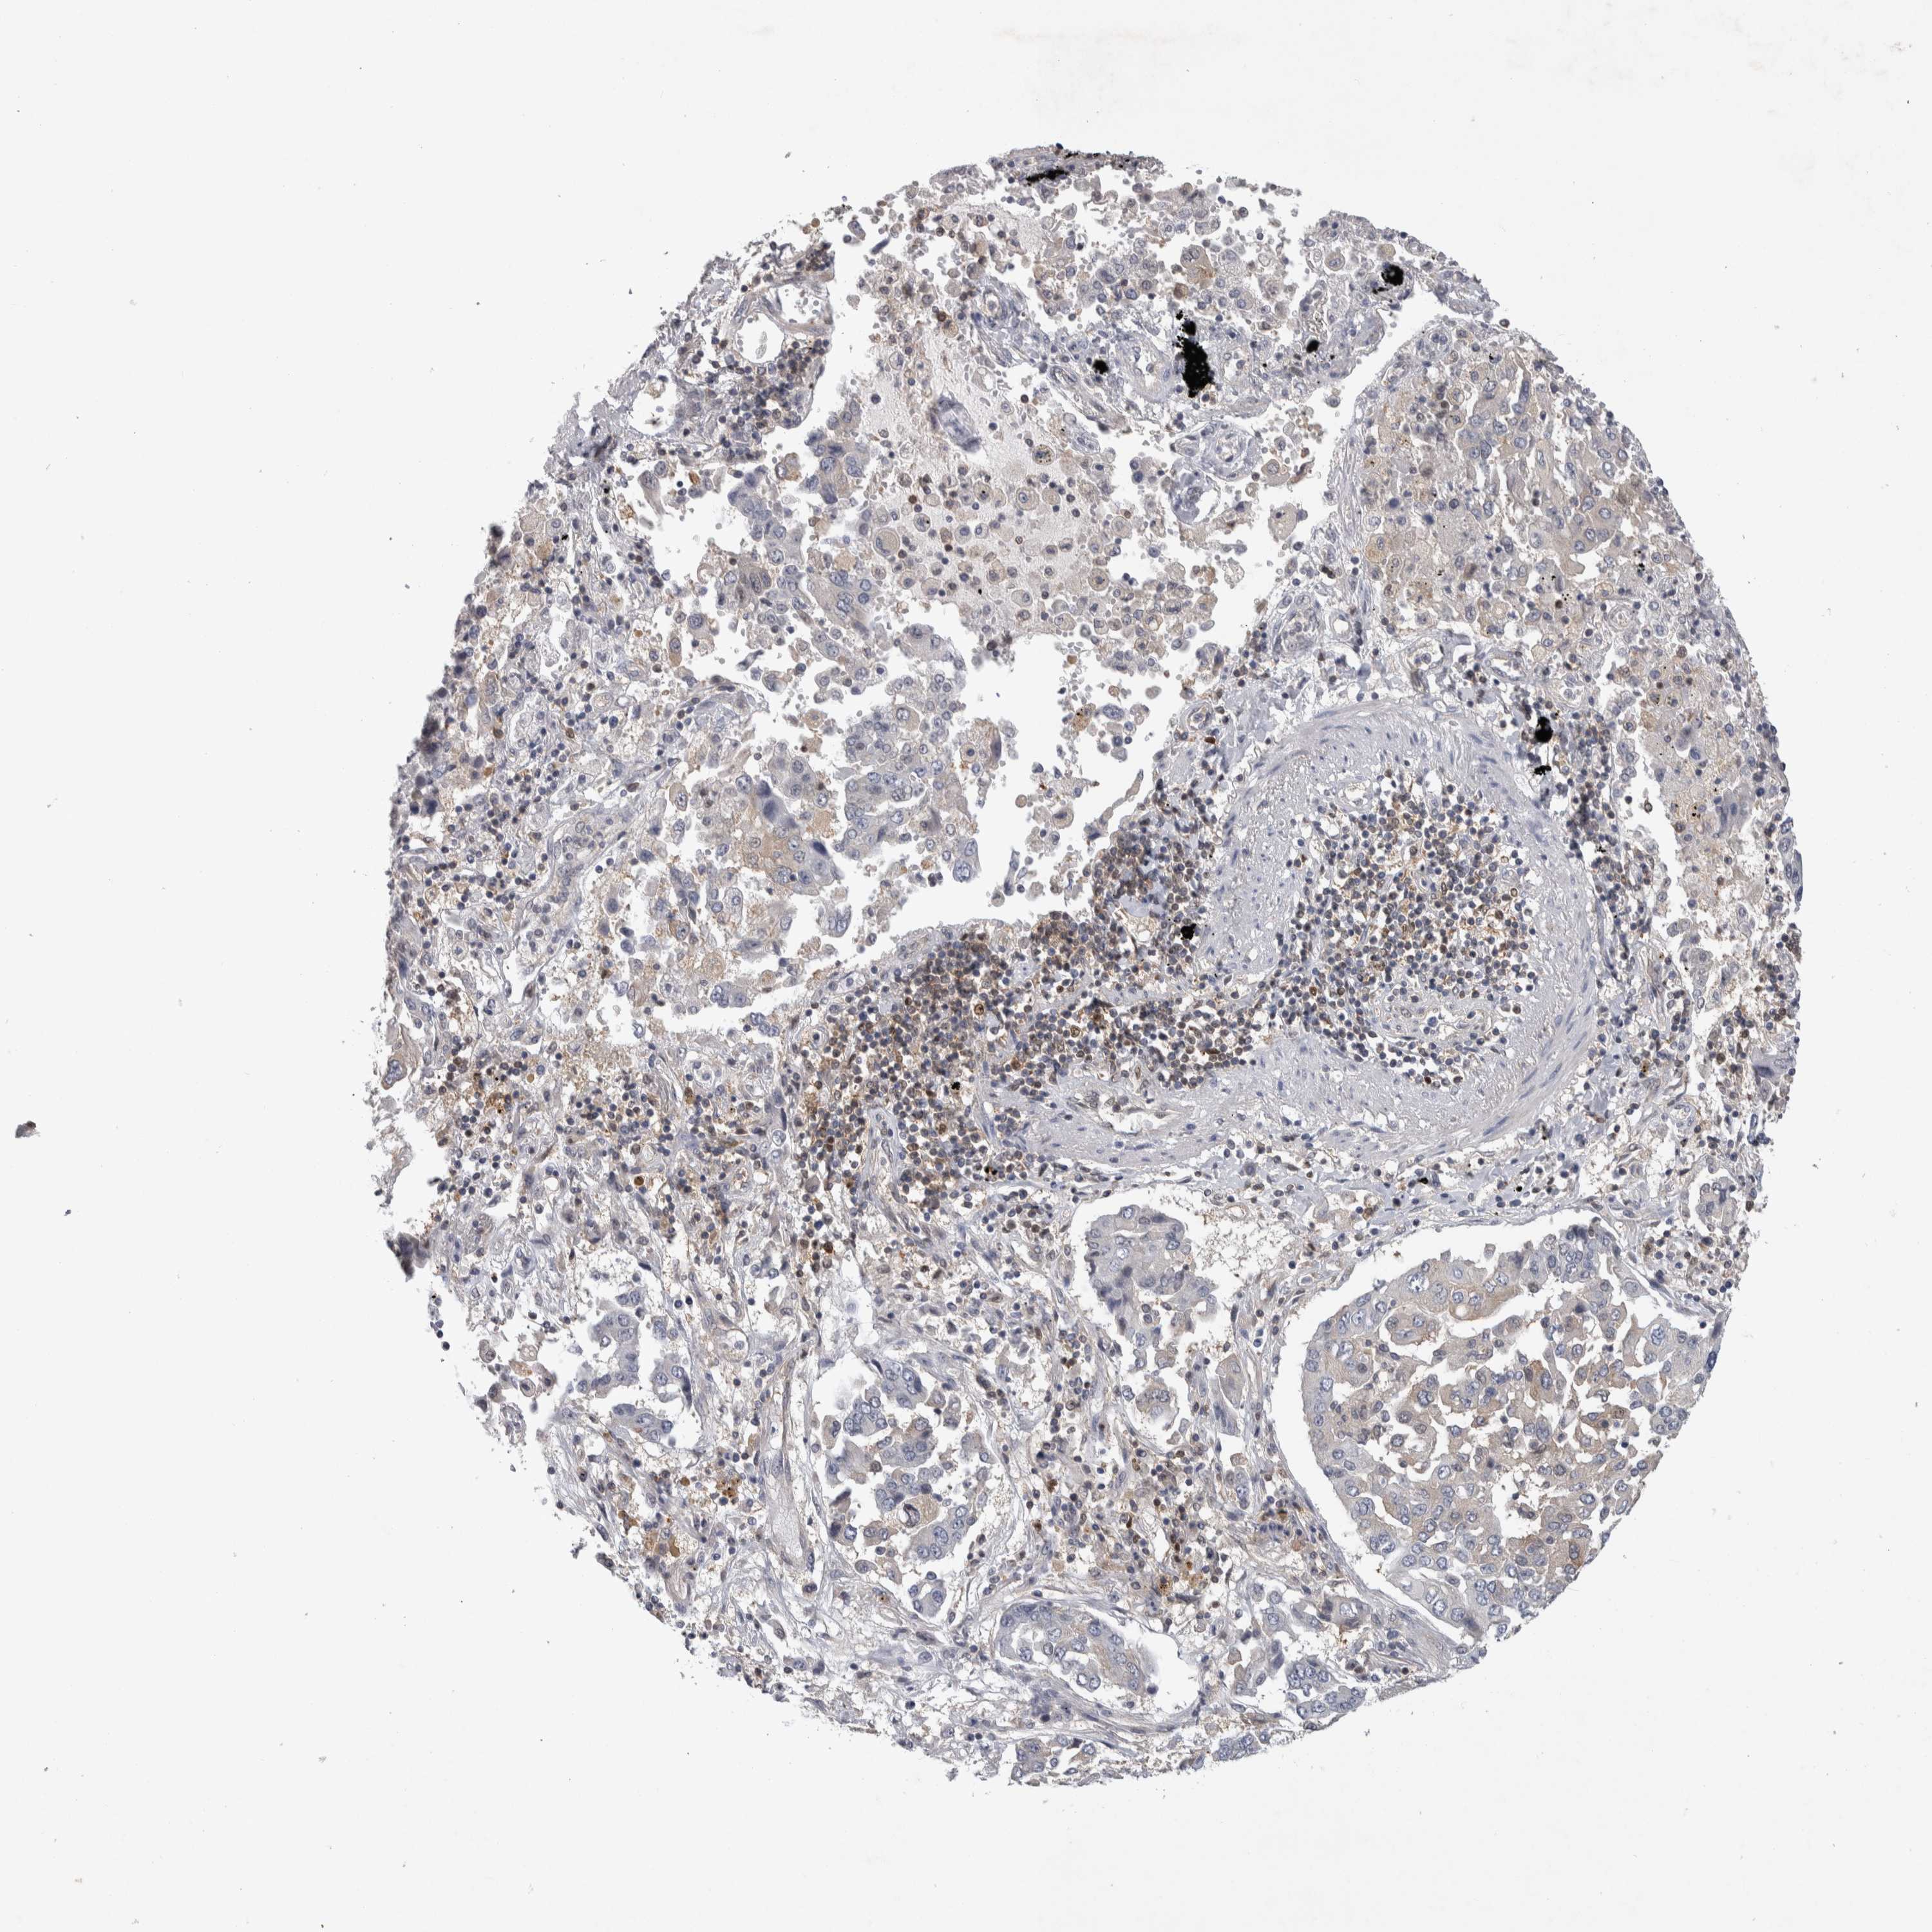

LUNG SQUAMOUS CELL CARCINOMA (TCGA) - Interactive survival scatter ploti

The Survival Scatter plot shows the clinical status (i.e. dead or alive) for all individuals in the patient cohort, based on the same data that underlies the corresponding Kaplan-Meier plots. Patients that are alive at last time for follow-up are shown in blue and patients who have died during the study are shown in red.

The x-axis shows the expression levels (FPKM) of the investigated gene in the tumor tissue at the time of diagnosis. The y-axis shows the follow-up time after diagnosis (years). Both axes are complimented with kernel density curves demonstrating the data density over the axes. The top density plot shows the expression levels (FPKM) distribution among dead (red) and alive patients (blue). The right density plot shows the data density of the survived years of dead patients with high and low expression levels respectively, stratified using the cutoff indicated by the vertical dashed line through the Survival Scatter plot. This cutoff is automatically defined based on the FPKM cutoff that minimizes the p-score. The cutoff can be changed by dragging the vertical line or by entering a cutoff value in the square labeled "Current cut-off".

Under the Survival Scatter plot the p-score landscape (black curve; left axis) is shown together with dead median separation (red curve; right axis). Dead median separation is the difference in median mRNA expression between patients who have died with high and low expression, respectively. It is calculated as follows: median FPKM expression of dead patients with high expression - median FPKM expression of dead patients with low expression. This is intended to aid the user in visually exploring custom cutoffs and the associated p-scores and dead median separation.

Individual patient data is displayed and can be filtered by clicking on one or more of the category buttons on the top of the page. Categories describing expression level and patient information include: high, low, alive, dead, female, male and tumor stages. The scale of the x-axis can be toggled between linear and log-scale by clicking on the "x log" button. Mouse-over function shows TCGA ID, patient information and mRNA expression (FPKM) for each patient.

& Survival analysisi

Kaplan-Meier plots summarize results from analysis of correlation between mRNA expression level and patient survival. Patients were divided based on level of expression into one of the two groups "low" (under cut off) or "high" (over cut off). X-axis shows time for survival (years) and y-axis shows the probability of survival, where 1.0 corresponds to 100 percent.

NFKB2 is not prognostic in Lung Squamous Cell Carcinoma (TCGA)

Current cut offi

Current cut-off shows the cut-off (FPKM) currently selected. It may be changed manually. When the current cut-off is changed, the vertical dashed line indicating cut-off, the interactive survival scatter plot and the Kaplan-Meier curve will be automatically adjusted to show results accordingly.

:

Best expression cut offi

Based on the FPKM value of each gene, patients were classified into two groups and association between prognosis (survival) and gene expression (FPKM) was examined. The best expression cut-off refers the FPKM value that yields maximal difference with regard to survival between the two groups at the lowest log-rank P-value. Best expression cut-off was selected based on survival analysis .

When clicking on this number, the vertical dashed line indicating cut-off, the interactive survival plot, and the Kaplan-Meier curve will be adjusted to show results based on the best expression cut-off.

: 24.87

Median expressioni

Median expression refers to the median FPKM value calculated based on the gene expression (FPKM) data from all patients in this dataset. When clicking on this number, the vertical dashed line indicating cut-off, the interactive survival plot, and the Kaplan-Meier curve will be adjusted to show results based on the median expression.

: N/A

Median follow up timei

Median follow up time refers to the median time (years) after diagnosis with this type of cancer, based on clinical data from all patients in this dataset.

P scorei

Log-rank P value for Kaplan-Meier plot showing results from analysis of correlation between mRNA expression level and patient survival.

N/A

5-year survival highi

5-year survival for patients with higher expression than the expression cutoff.

For melanoma and glioma, 3-year survival is shown.

5-year survival lowi

5-year survival for patients with lower expression than the expression cutoff.

TCGA RNA samplesi

RNA-seq data is reported as average FPKM (number Fragments Per Kilobase of exon per Million reads), generated by the The Cancer Genome Atlas (TCGA) .

Normal distribution across the dataset is visualized with box plots, shown as median and 25th and 75th percentiles. Points are displayed as outliers if they are above or below 1.5 times the interquartile range. FPKM values of the individual samples are presented next to the box plot.

Average pTPM 30.7

Number of samples 489